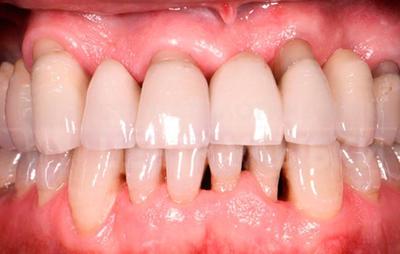

- Локализованный (очаговый) пародонтит — воспаление поражает один или несколько зубов, а также ткани, прилегающие к ним. Чаще всего протекает в острой форме. При отсутствии лечения переходит в диффузный пародонтит, заражая здоровые зубы.

Фото 2. Локальный пародонтит. Воспалены несколько зубов, в области воспаления наблюдается кровотечение.

- Генерализованный (диффузный) пародонтит — воспаление поражает весь зубной ряд или практически все зубы, а также ткани, прилегающие к ним. Чаще всего протекает в хронической форме. Нередко приводит к потере зубов.

Внимание! В начале заболевания, распространенность обычно локализованная. Именно в этот период важно проконсультироваться со специалистом и начать лечение. Вылечить пару зубов будет проще и быстрее, чем весь зубной ряд.